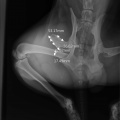

Tehtud ortopeediline op Hoiuaiga Kliinikus. Kõik on korras. Käpp pareneb!

Tagumise käpa luumurd.